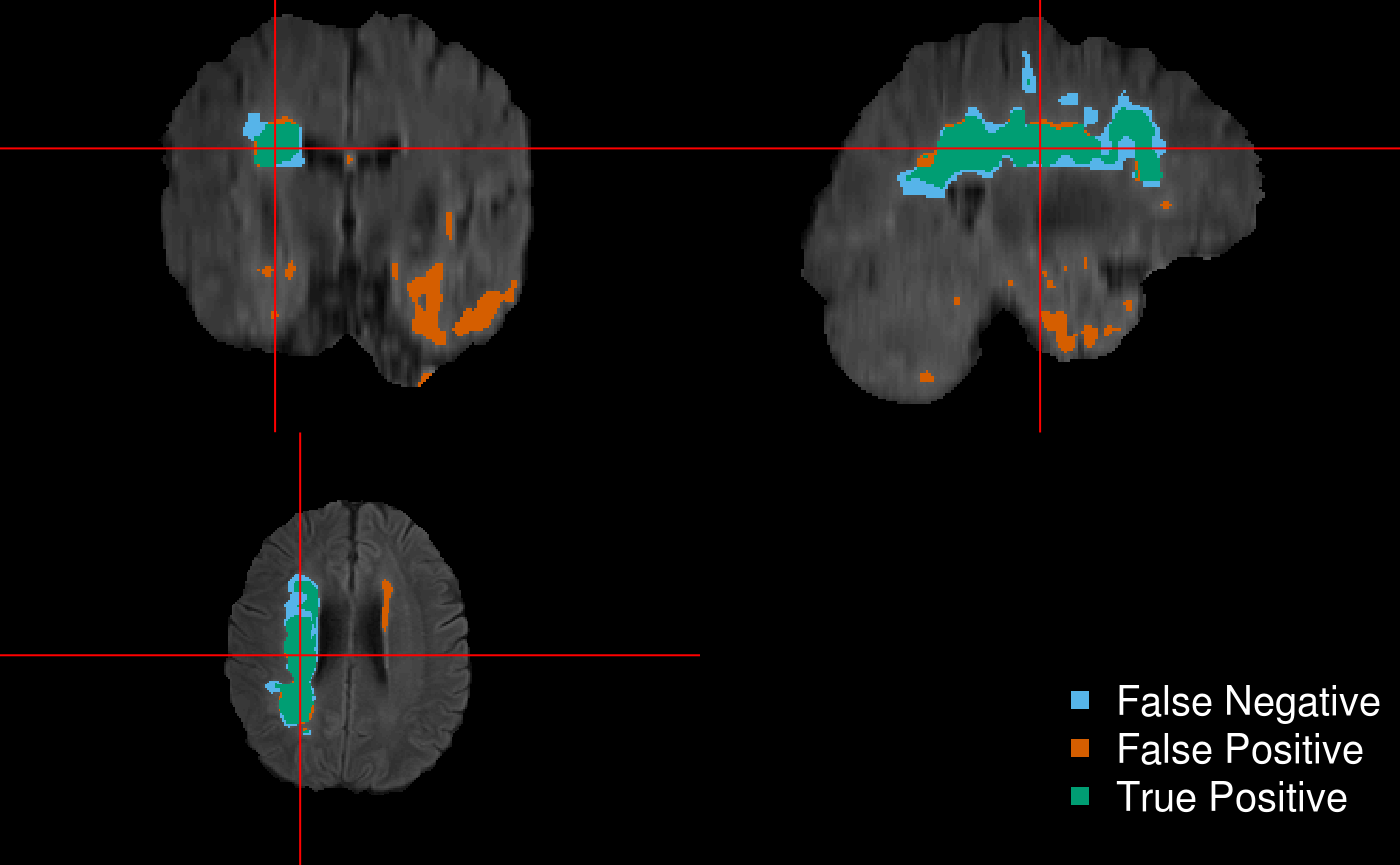

And now make the prediction image and visualize it…

# comparison to ground truth

y_img = readnii(test.y.file[[1]]) # 230x230x154

double_ortho(x = y_img, y = test.preds[[1]] > 0.5,

NA.x = TRUE,

NA.y = TRUE,

xyz = xyz(y_img),

col = "white",

col.y = "white") #binary prediction